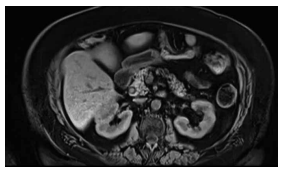

Mulher de 55 anos, com antecedente de gastroplastia

em Y de Roux, com colecistectomia há 1 ano por obesidade, evolui com dor em hipocôndrio direito, colúria e

icterícia.

Exames laboratoriais mostram bilirrubina total de 5,8 mg/dL (direta 4,4), fosfatase alcalina de 690 U/L e leucocitose discreta.

Realizou-se uma ressonância, conforme mostra a imagem a seguir.